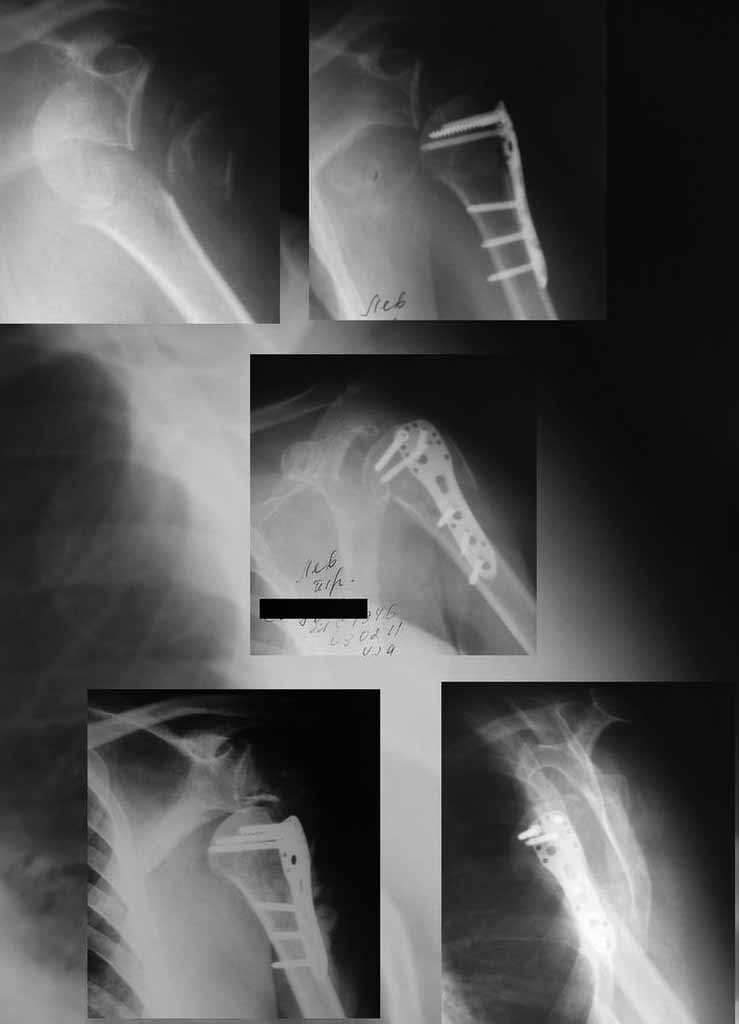

Уважаемы коллеги! Прошу помочь определиться с тактикой лечения пациентки. В феврале в отделение поступила пациентка с оскольчатым переломо-вывихом головки плечевой кости. Выполнена операция -остеосинтез блокируемой пластиной. Костная пластика не производилась. На контрольных рентгенограммах остается сублюксация головки и смещение большого бугорка. Интраоперационно бугорок подшивался с помощью лавсановых нитей. Послеоперационно: ношение косыночной повязки и пассивные движения в плечевом суставе в течение 2,5-х месяцев без особенностей. Через 2,5 месяца при попытке выполнения пассивно-активных движений произошел передний вывих плечевой кости.Вся реабилитация производилась по месту жительства. Таким образом существование вывиха в течение 1 месяца. Боли не беспокоят. Нейрососудистых нарушений в конечности нет. Что вы можете посоветовать: пластику, эндопротез, артродез? Заранее спасибо.

мне кажется ,что на послеоперационном снимке, также имеется сублюксация головки.сколько годов пациентке?

Уважаемый коллега. На мой взгляд имеющаяся дислокация головки обусловлена на мой взгляд имеющейся у пациента обширной травмой ротаторного аппарата. В пользу данной точки зрения могу привести следующее: на представленных Вами рентгенограммах хорошо заметен отрыв большого бугорка со смещением отломков который как известно является точкой прикрепления коротких наружных ротаторов плеча. Последующая миграция данного фрагмента и неполноценная репозиция его при первичном остеосинтезе с нестабильной фиксацией на мой взгляд и обусловили создавшуюся ситуацию. то что пациента не беспокоят боли позволю подвергнуть сомнению поскольку сам занимаюсь хирургией плеча и с подобными ситуациями сталкивался неоднократно. На мой взгляд в настоящее время целесообразно проведение повторного оперативного вмешательства с адекватным восстановлением ротаторного аппарата, поскольку дальнейшее затягивание сложившейся ситуации уменьшает шанс на успех данного вмешательства.

Набор мелких снимков не отражает истинную картину суставной поверхности лопатки, а также качество репозиции головки плеча. Необходимо доказать аксиальным снимком наличие покрытия головки. Правильная маркировка на рентген снимках и соответствие с выставленным диагнозом гарантирует от ошибок со стороной во время операции!

Здесь результат похожего случая, больная 87 лет, отягощенная сердечными делами и два года назад установка pacemaker и нескольких стентов. На третий день, сегодня утром сделали операцию. Послеоперационный псевдовывих связанный с релаксацией мышц и общим обезболиванием.

Для адекватного лечения необходимо знать состояние костного компонента - нужно КТ с артрографией что поможет частично оценить состояние сухожилий и лабриум. Уже по снимку можно сказать что существует большой костный дефект в задне-наружном сегменте.